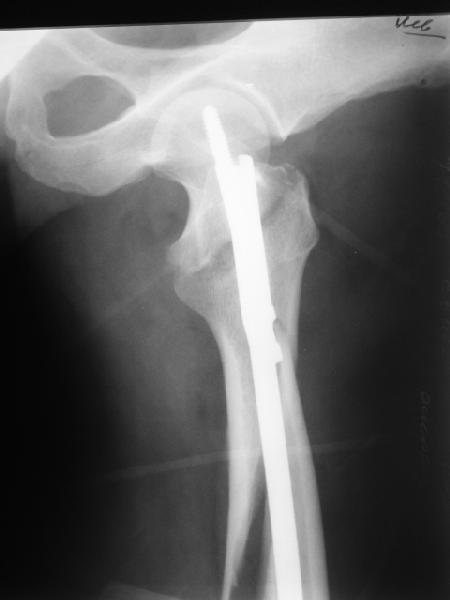

Как раз недавно у меня был примерный случай: больному 36 лет, поступил ночью, травма в результате мотоциклетной аварии, кроме чрезвертельного и спирального перелома левого бедра имеется переломы костей предплечья с этой же стороны. Скелетное вытяжение, а на следующий день больной про оперирован на ортопедическом столе с дистракцией. Чтобы не расколоть чрезвертельный перелом провели временную спицу ближе к переднему кортексу, из малого разреза костодержатель для репозиции, а фиксацию провели антиградным штифтом. Этапы операции на снимках.

DK> фиксацию провели антеградным штифтом.

Да, сейчас это и у нас самый напрашивающийся выбор. Сделали гвоздем ChM, картинки в приложении.